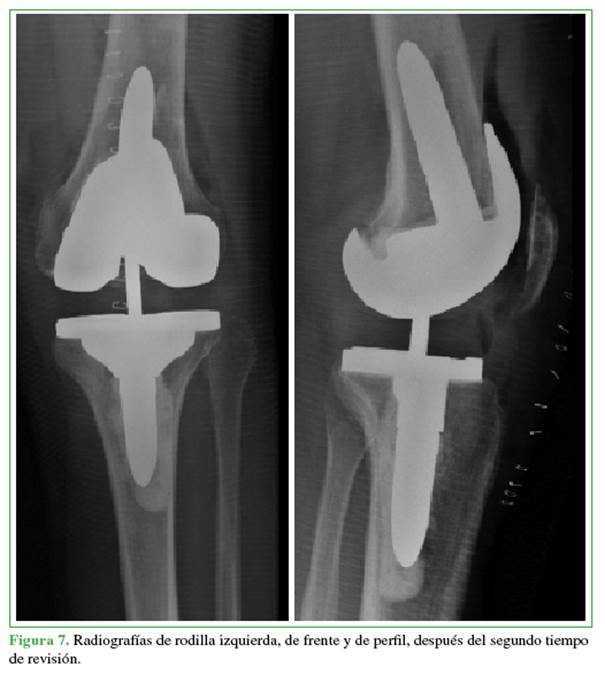

A los tres meses de la cirugía, el paciente tenía dolor en reposo y durante la actividad, derrame articular recurrente, una masa ocupante en el receso subcuadricipital y flexió́n limitada a 90° (Figura 3). La herida estaba cicatrizada, sin eritema ni aumento de temperatura y no se detectó́ inestabilidad en los planos coronal y sagital. Como el tratamiento con analgésicos y kinesiología no tuvo éxito, a los seis meses de la operació́n, se realizó́ una artrocentesis, se obtuvo un líquido hemorrágico, sin aislamiento de germen. A los siete meses de la intervenció́n, en la radiografía de frente, de control, se observó́ una imagen radiolúcida en las zonas 1-2 de la clasificació́n de la Knee Society, sugestivas de aflojamiento temprano de la pró́tesis13 (Figura 4).